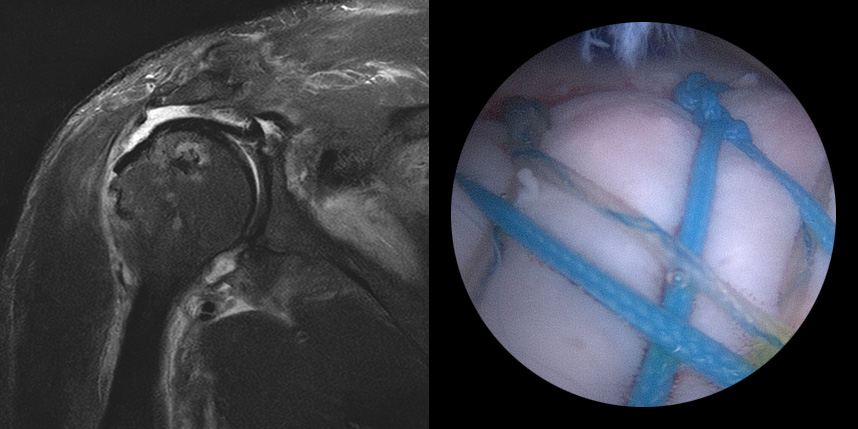

관절내시경은 작은 절개 부위로 고해상도 카메라를 삽입하여 관절 내부를 관찰하는 방법으로

화면을 통해 병변 부위를 직접 확인하면서 손상 정도에 따라 파열된 힘줄을 봉합하거나 염증을 제거할 수 있습니다.

손상된 조직을 봉합 혹은 제거하기 위해선 작은 수술 도구가 필요하며, 이들 도구는 작은 추가 절개구로 삽입되어 사용됩니다.